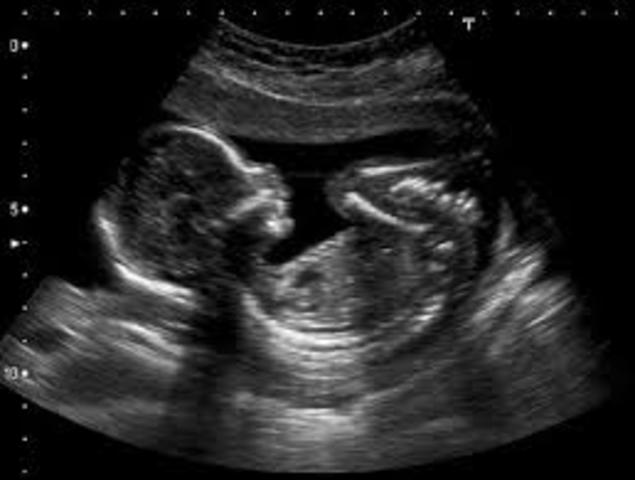

• 3rd Month

3rd Month

12 weeks:

1. You can hear baby's heart beat.

2. All organs work.

3. Arms, legs, and hands fully developed.